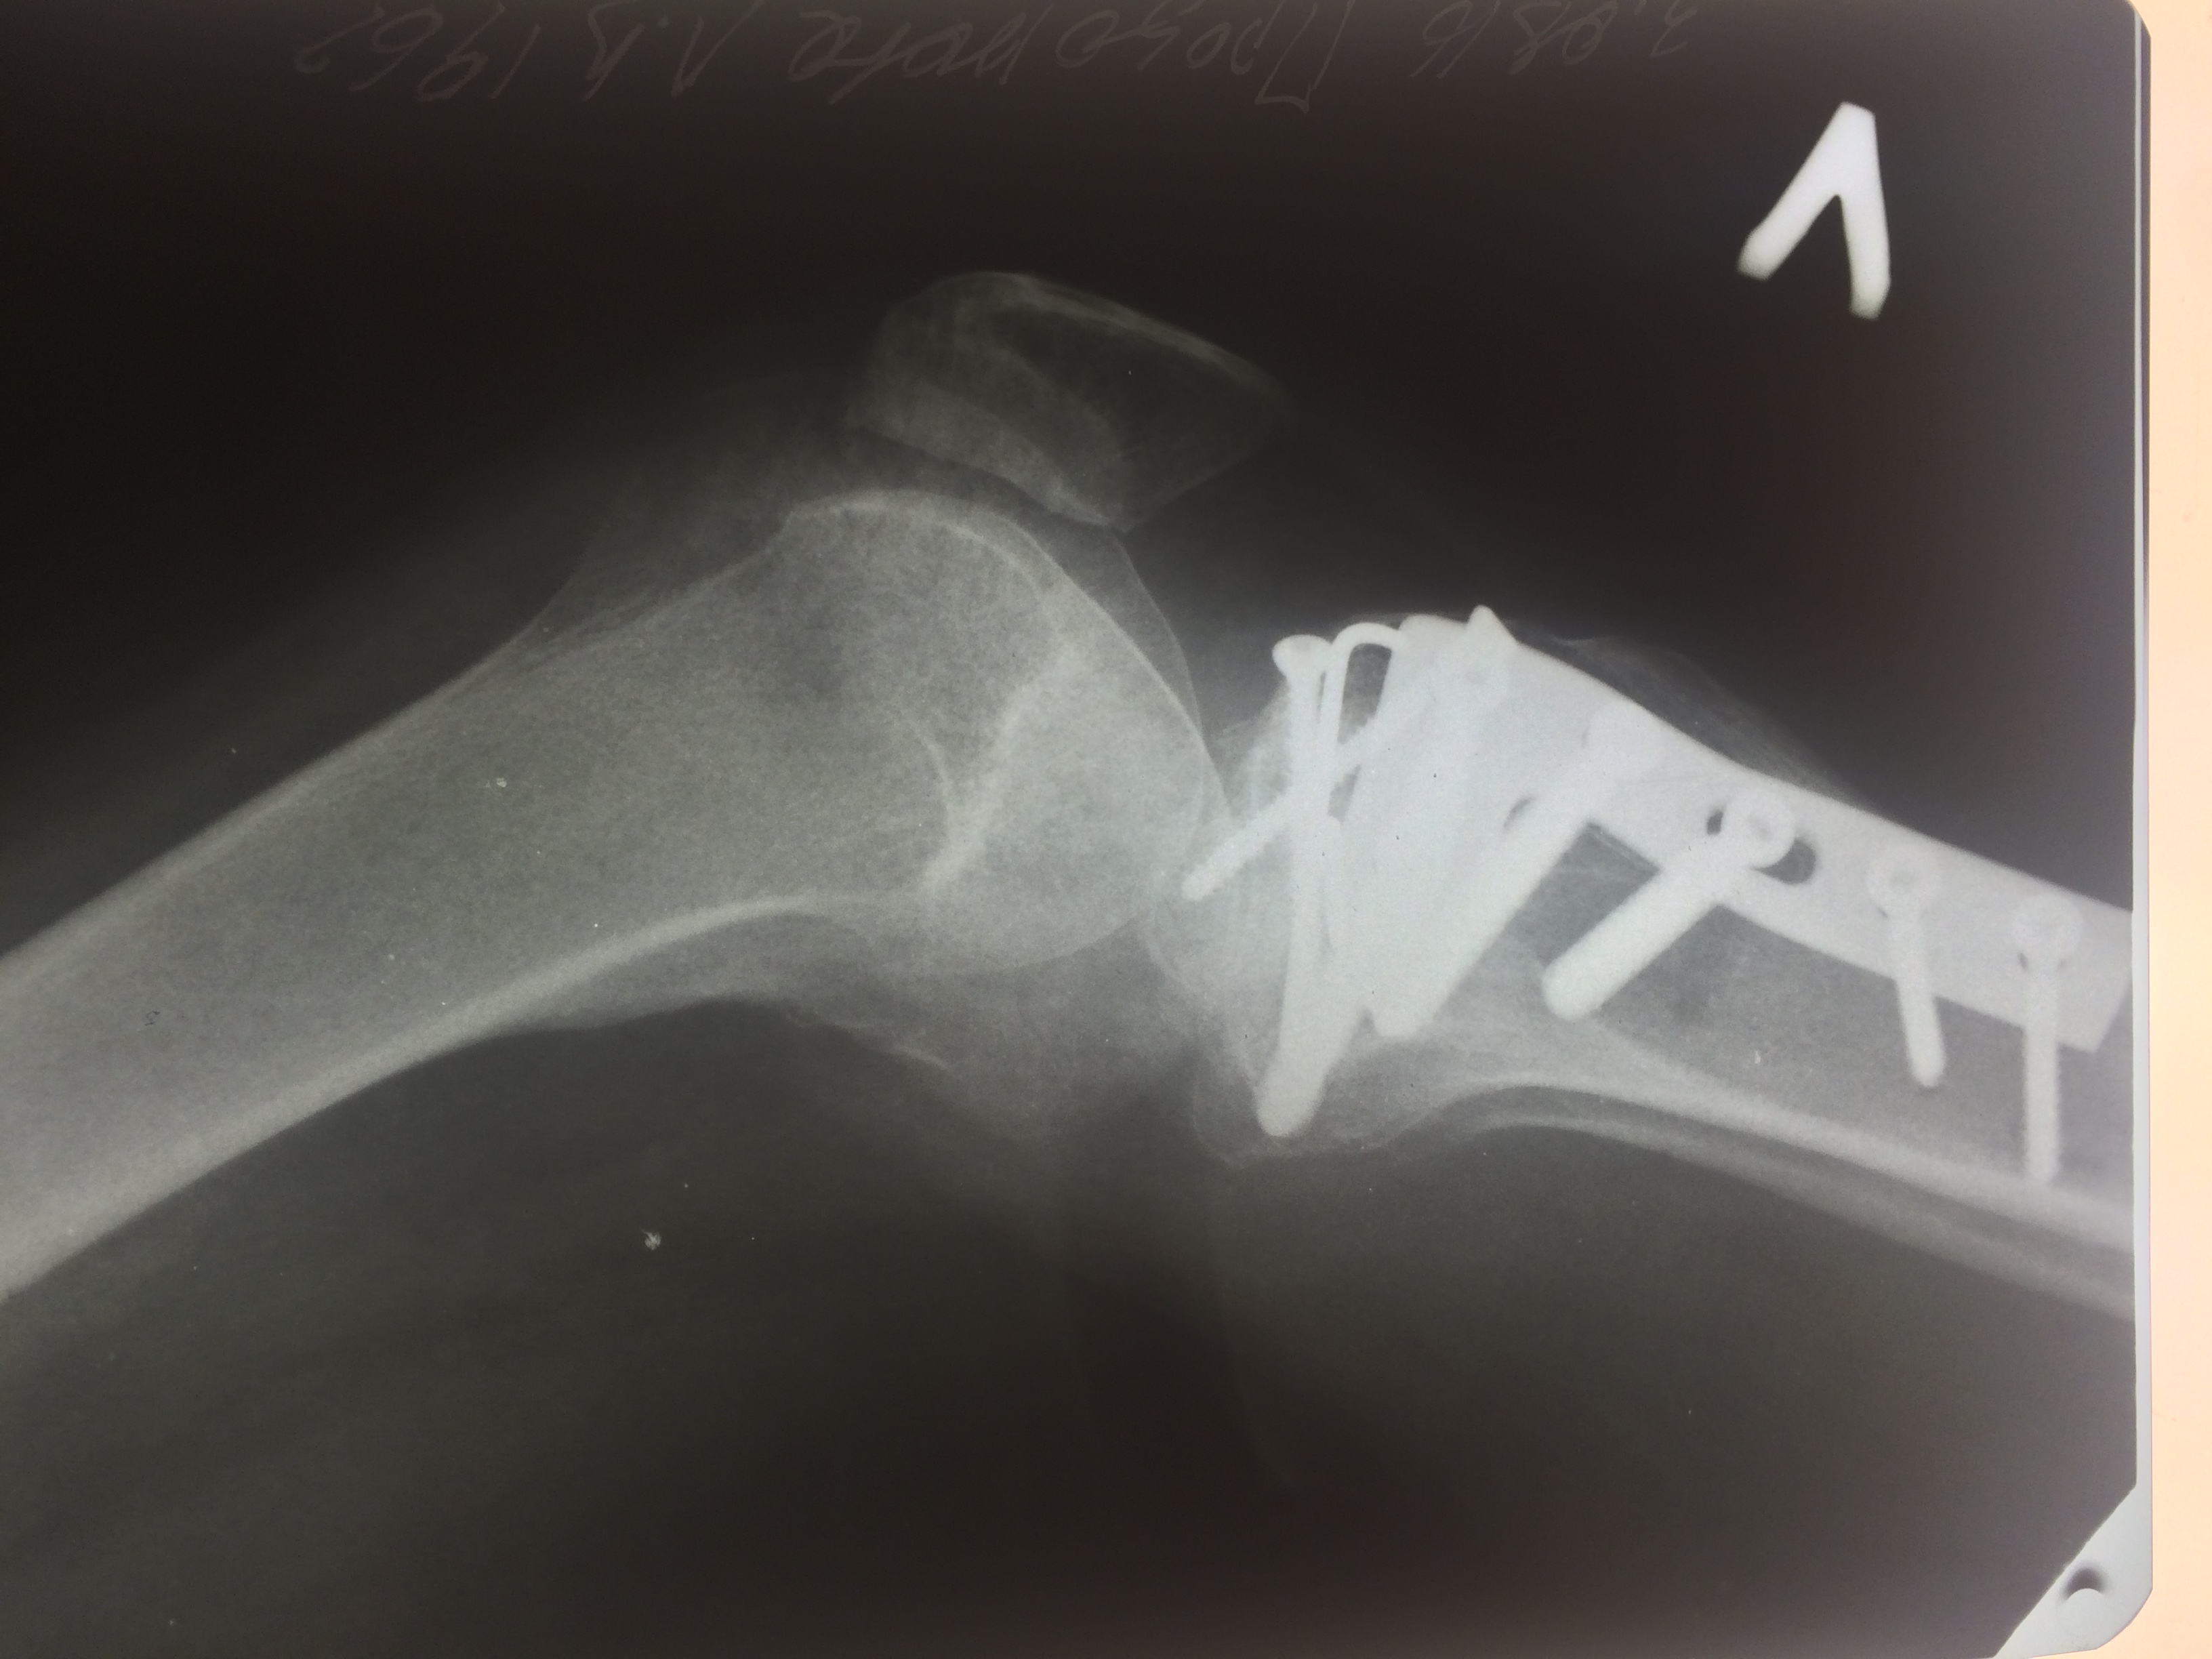

Операция - открытая репозиция, остеосинтез большеберцовой кости опорной пластиной с костной ксенопластикой маетриалом "Остеоматрикс". На контрольных снимках в три и шесть месяцев имеется консолидация перелома, миграции фиксатора нет, имеется остеоинтеграция ксенопластического материала. Функция коленного сустава полная.

Отдаленные результаты через 6 (шесть) месяцев